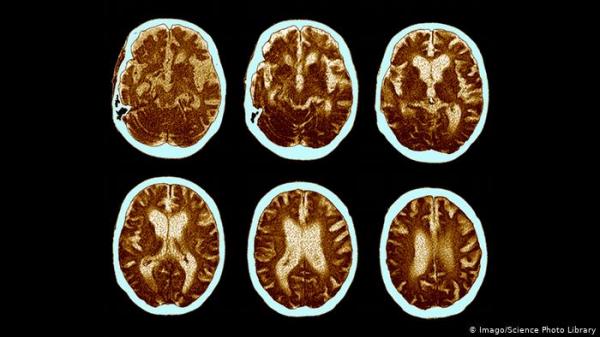

دراسة: هذا المزيج الغذائي يحد من آثار مرض الزهايمر